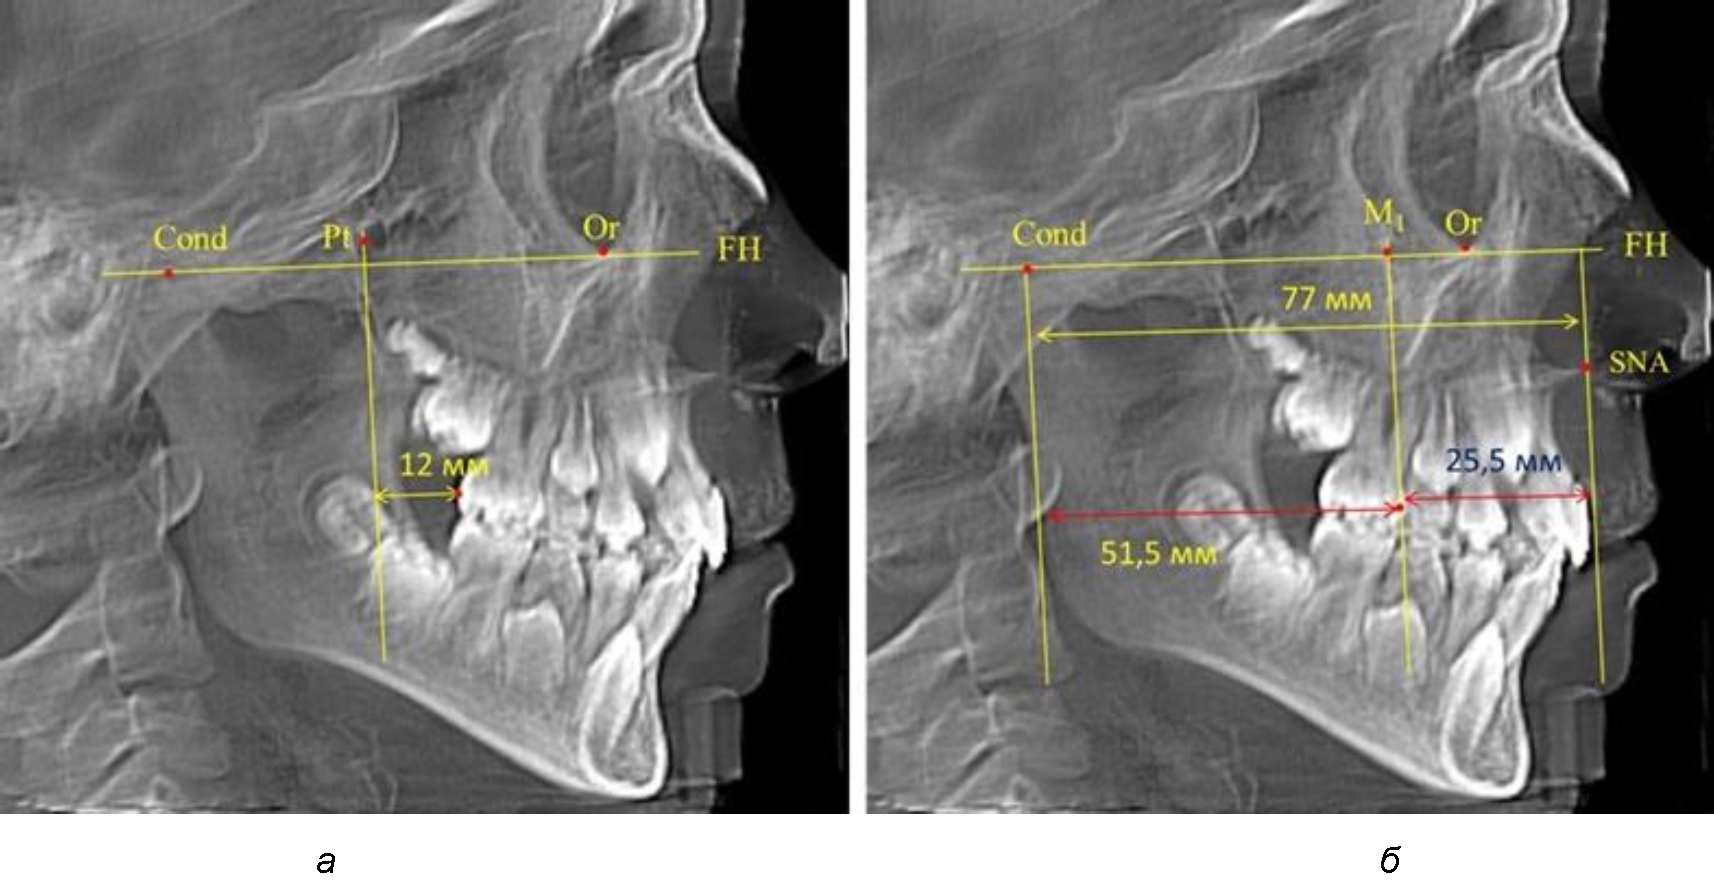

Так, при расстоянии от крыловидной вертикальной плоскости PTV до дистальной поверхности верхнего первого постоянного моляра в 13 мм сагиттальный размер гнатического отдела был 82 мм. При этом отношение кондилярно-спинального расстояния к кондилярно-молярному размеру (54,5) было близким к коэффициенту 1,5, что представлено на рис. 2.

В то же время при увеличенном расстоянии от крыловидной вертикальной плоскости PTV до дистальной поверхности верхнего первого постоянного моляра, равное 23 мм, сагиттальный размер гнатического отдела составил 92 мм. При этом отношение кондилярно-спинального расстояния к кондилярно-молярному размеру (30,5), так же, как и при малых размерах, было близким к коэффициенту 1,5, что представлено на рис. 3.

Рис. 2. Особенности положения первых моляров по R. E. McDonald (а) и по предложенному методу (б) при уменьшенном молярно-крыловидном расстоянии

Рис. 3. Особенности положения первых моляров по R. E. McDonald (а) и по предложенному методу (б) при увеличенном молярно-крыловидном расстоянии